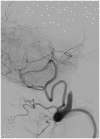

In this review article, we summarized the current advances in rescue management for reperfusion therapy of acute ischemic stroke from large vessel occlusion due to underlying intracranial atherosclerotic stenosis (ICAS). It is estimated that 24-47% of patients with acute vertebrobasilar artery occlusion have underlying ICAS and superimposed in situ thrombosis. These patients have been found to have longer procedure times, lower recanalization rates, higher rates of reocclusion and lower rates of favorable outcomes than patients with embolic occlusion. Here, we discuss the most recent literature regarding the use of glycoprotein IIb/IIIa inhibitors, angioplasty alone, or angioplasty with stenting for rescue therapy in the setting of failed recanalization or instant/imminent reocclusion during thrombectomy. We also present a case of rescue therapy post intravenous tPA and thrombectomy with intra-arterial tirofiban and balloon angioplasty followed by oral dual antiplatelet therapy in a patient with dominant vertebral artery occlusion due to ICAS. Based on the available literature data, we conclude that glycoprotein IIb/IIIa is a reasonably safe and effective rescue therapy for patients who have had a failed thrombectomy or have residual severe intracranial stenosis. Balloon angioplasty and/or stenting may be helpful as a rescue treatment for patients who have had a failed thrombectomy or are at risk of reocclusion. The effectiveness of immediate stenting for residual stenosis after successful thrombectomy is still uncertain. Rescue therapy does not appear to increase the risk of sICH. Randomized controlled trials are warranted to prove the efficacy of rescue therapy.